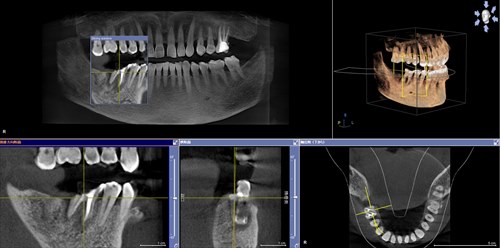

術後2ヶ月CT。うん、いい!